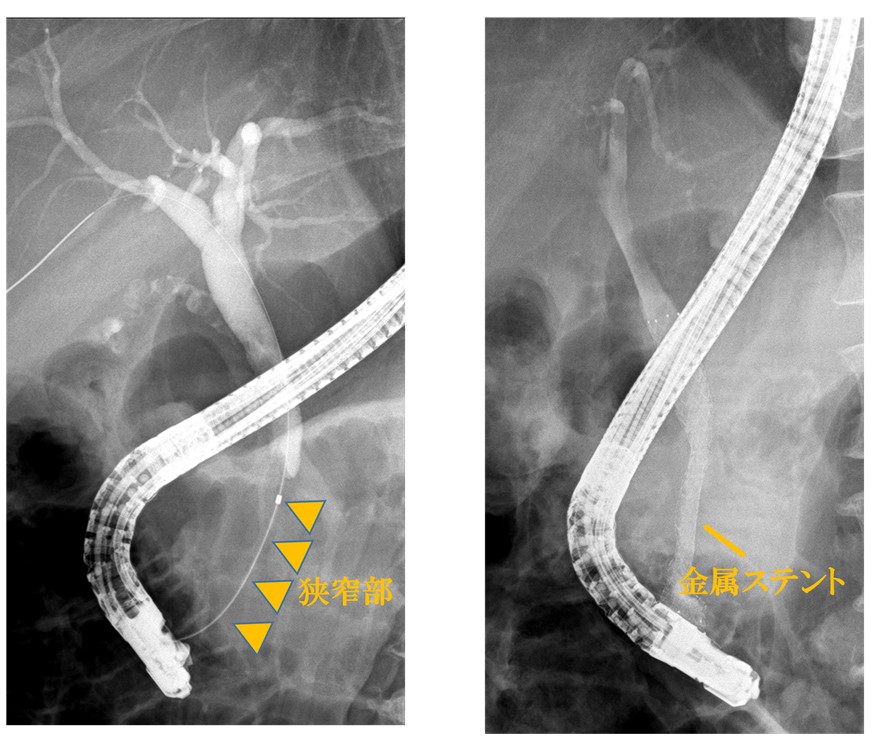

悪性の病気が疑われた場合には、画像検査(腹部超音波検査・CT・MRI・内視鏡検査等)により診断を行います。診断確定後は、手術での切除が可能な場合は迅速に手術を行います。すぐに切除することが難しい場合には、腫瘍内科と連携し化学療法を行っていきます。また、胆道がんによる胆管狭窄に対しては、内視鏡でステント(金属・プラスチック。図3)を留置し、胆管炎や黄疸を予防します。

図3 胆道がんによる胆管狭窄に対する胆管金属ステント